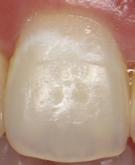

In the endodontic stage, conservative endodontic preparation and obturation with modern techniques are performed as they are for any tooth. All endodontic procedures are performed under an operating microscope to maximize visualization and illumination of the fracture line (Fig 1). The coronal portion of the newly placed gutta percha is removed 2 to 3 mm below the deepest extent of the crack in the affected canal to prepare for intraradicular barrier placement (Fig 2). Gutta percha is also removed 2 to 3 mm into the other noncracked canal orifices in the tooth to prepare for traditional orifice barriers. Microscopic transillumination with a fiber-optic light, in which an LED light probe is placed against buccal or lingual tissues overlying the roots, is utilized to illuminate the root and enhance visualization of the crack (Fig 3). A flowable resin-modified glassionomer or composite resin is then placed in this newly created void from the level of the gutta percha to the floor of the pulp chamber in all canal orifices (Fig 4). A composite resin core is then placed to permanently restore the endodontic access. If a temporary or permanent crown is not placed immediately after the endodontic procedures, the tooth is reduced

Fig 1. Microscopic visualization of the radicular extension of the crack (arrows) entering the canal.